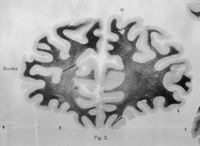

ImageChangement des fibres médullaires d'un côté à l'autre